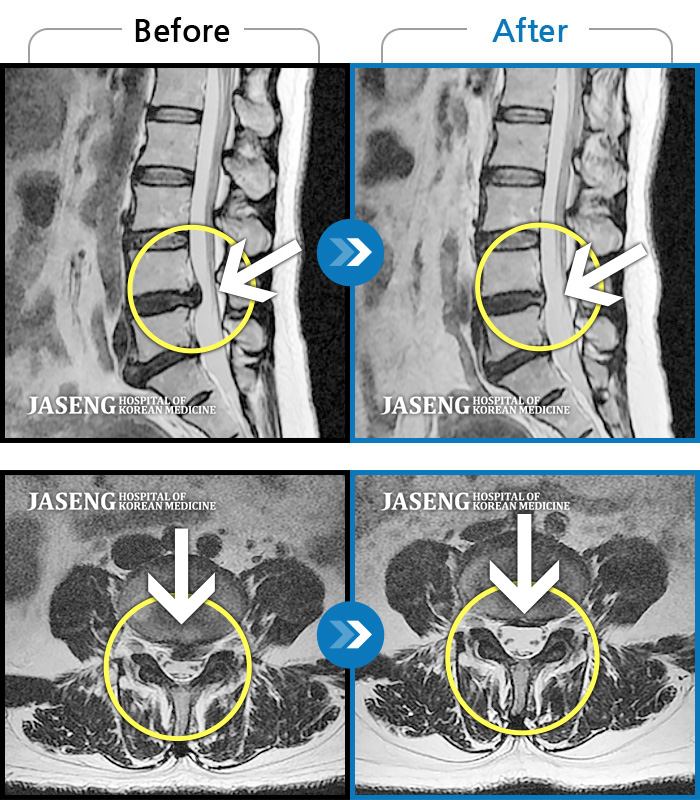

허리디스크

대전 · 김창연 원장

엉덩이의 왼쪽 부위 및 하지방사통이 심각하여 보행이 불가한 상태에서 내원하셨습니다.

촬영시기

2025.01.22 ~ 2025.08.09

2025.08.19